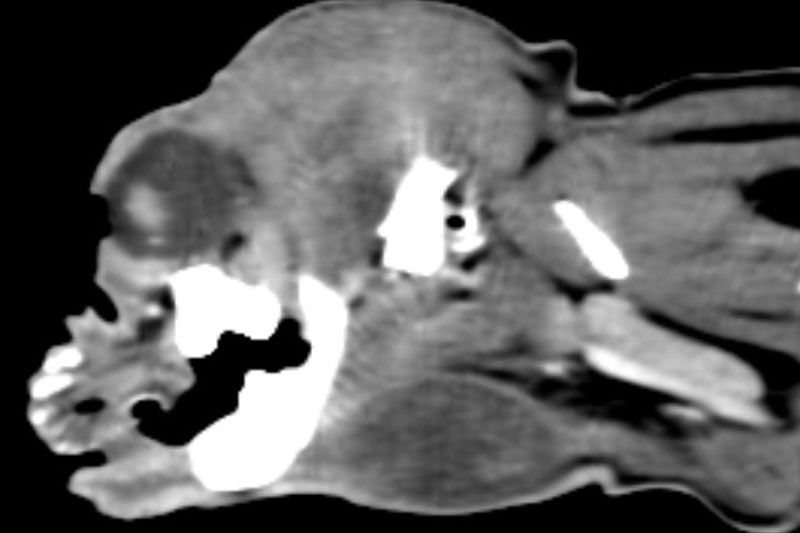

| 두부(머리) | 뇌종양, 두개골 골절, 중이염, 치주염, 안와(눈) 질환 등 |